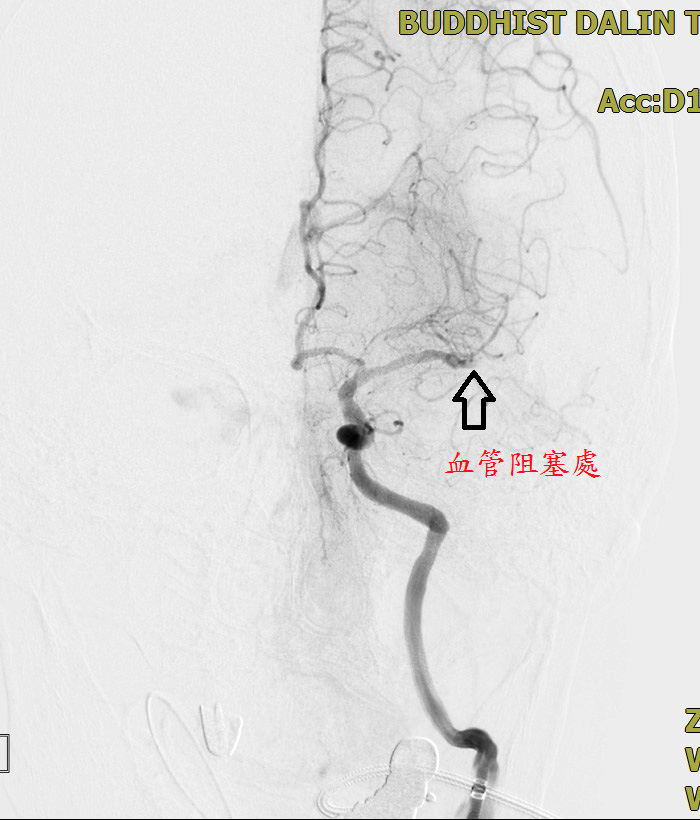

邱孟祈醫師表示,簡阿嬤當時突然右側無力、意識不清,懷疑是急性腦中風,經電腦斷層檢查確認並非出血性腦中風,因在發病一個多小時內即到院,送醫及時,先施打血栓溶解劑,並做電腦斷層血管攝影,確認是左側大腦動脈阻塞,在六小時內都可以進行機械取栓。經與影像醫學科黃厚期醫師合作,搭配血管攝影,從血管中將阻塞的血栓取出,順利打通血管。邱孟祈醫師指出,這類病人若未及時治療,有八九成可能會終生臥床,甚至導致死亡。

取栓前與取栓後的影像對比,可看出原本阻塞的血管被全部打通,血流恢復順暢。